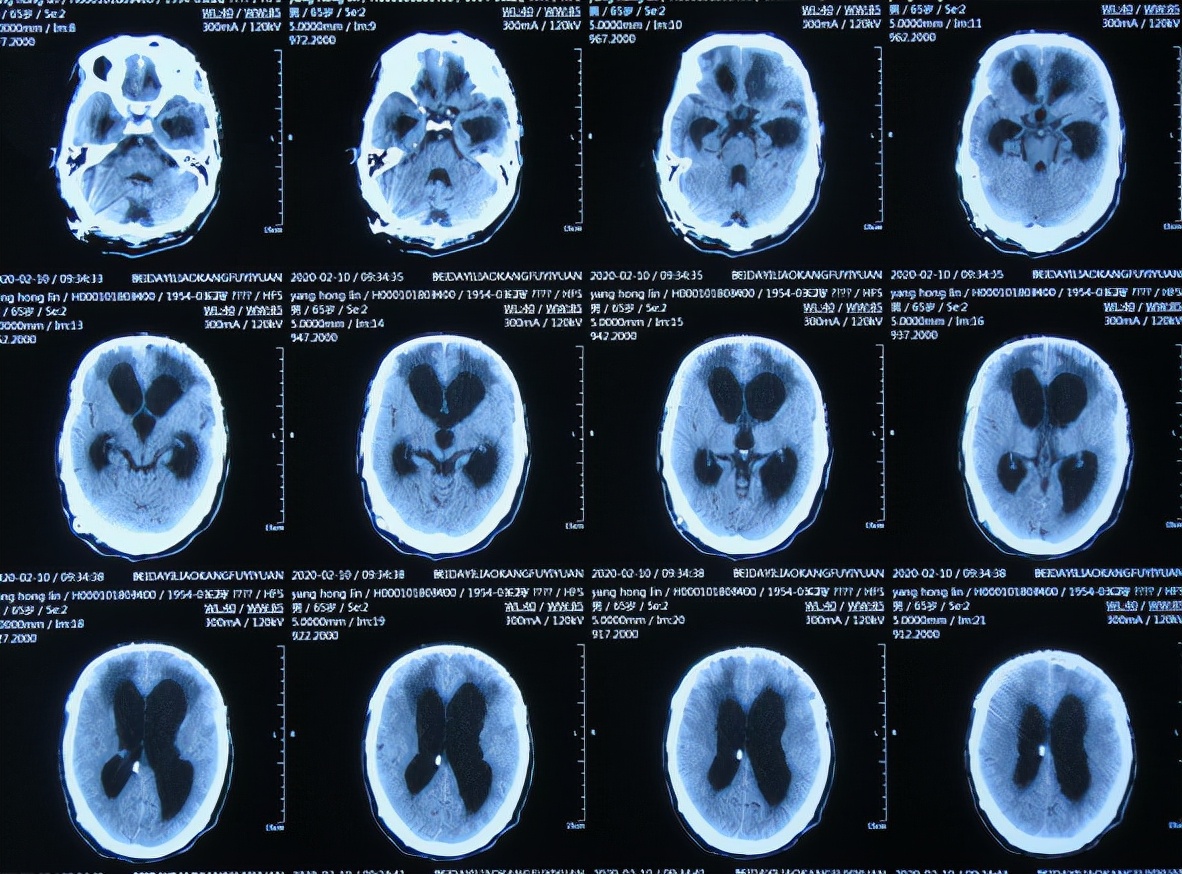

2019年10月20日患者骑电动车在马路上行驶时被大货车撞倒,当时意识清楚,只感到有些头晕,未在意就自行回家,但回家后约3-4小时出现头晕加重,并伴有恶心呕吐的症状,家人急送到当地的河北省邯郸市某医院,查头颅CT示脑出血( 图-1 );既往病史2015年曾因头部外伤致硬膜下血肿,进行了钻孔引流术。

图-1: 2019年10月20日头颅CT